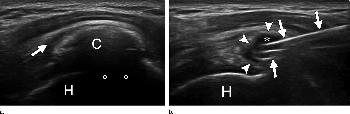

Figure 4. US images show supraspinatus calcification in a 37-year-old man. (a) Calcific deposit (C) can be clearly seen with moderate acoustic shadowing (circles). Subacromial bursitis (arrow) can be seen. (b) End of treatment. Most calcific material was removed from calcification (∗) with double-needle procedure. Only a thin calcific wall (arrowheads) was left. Needles (arrows) are still inside calcification. H = humeral head.